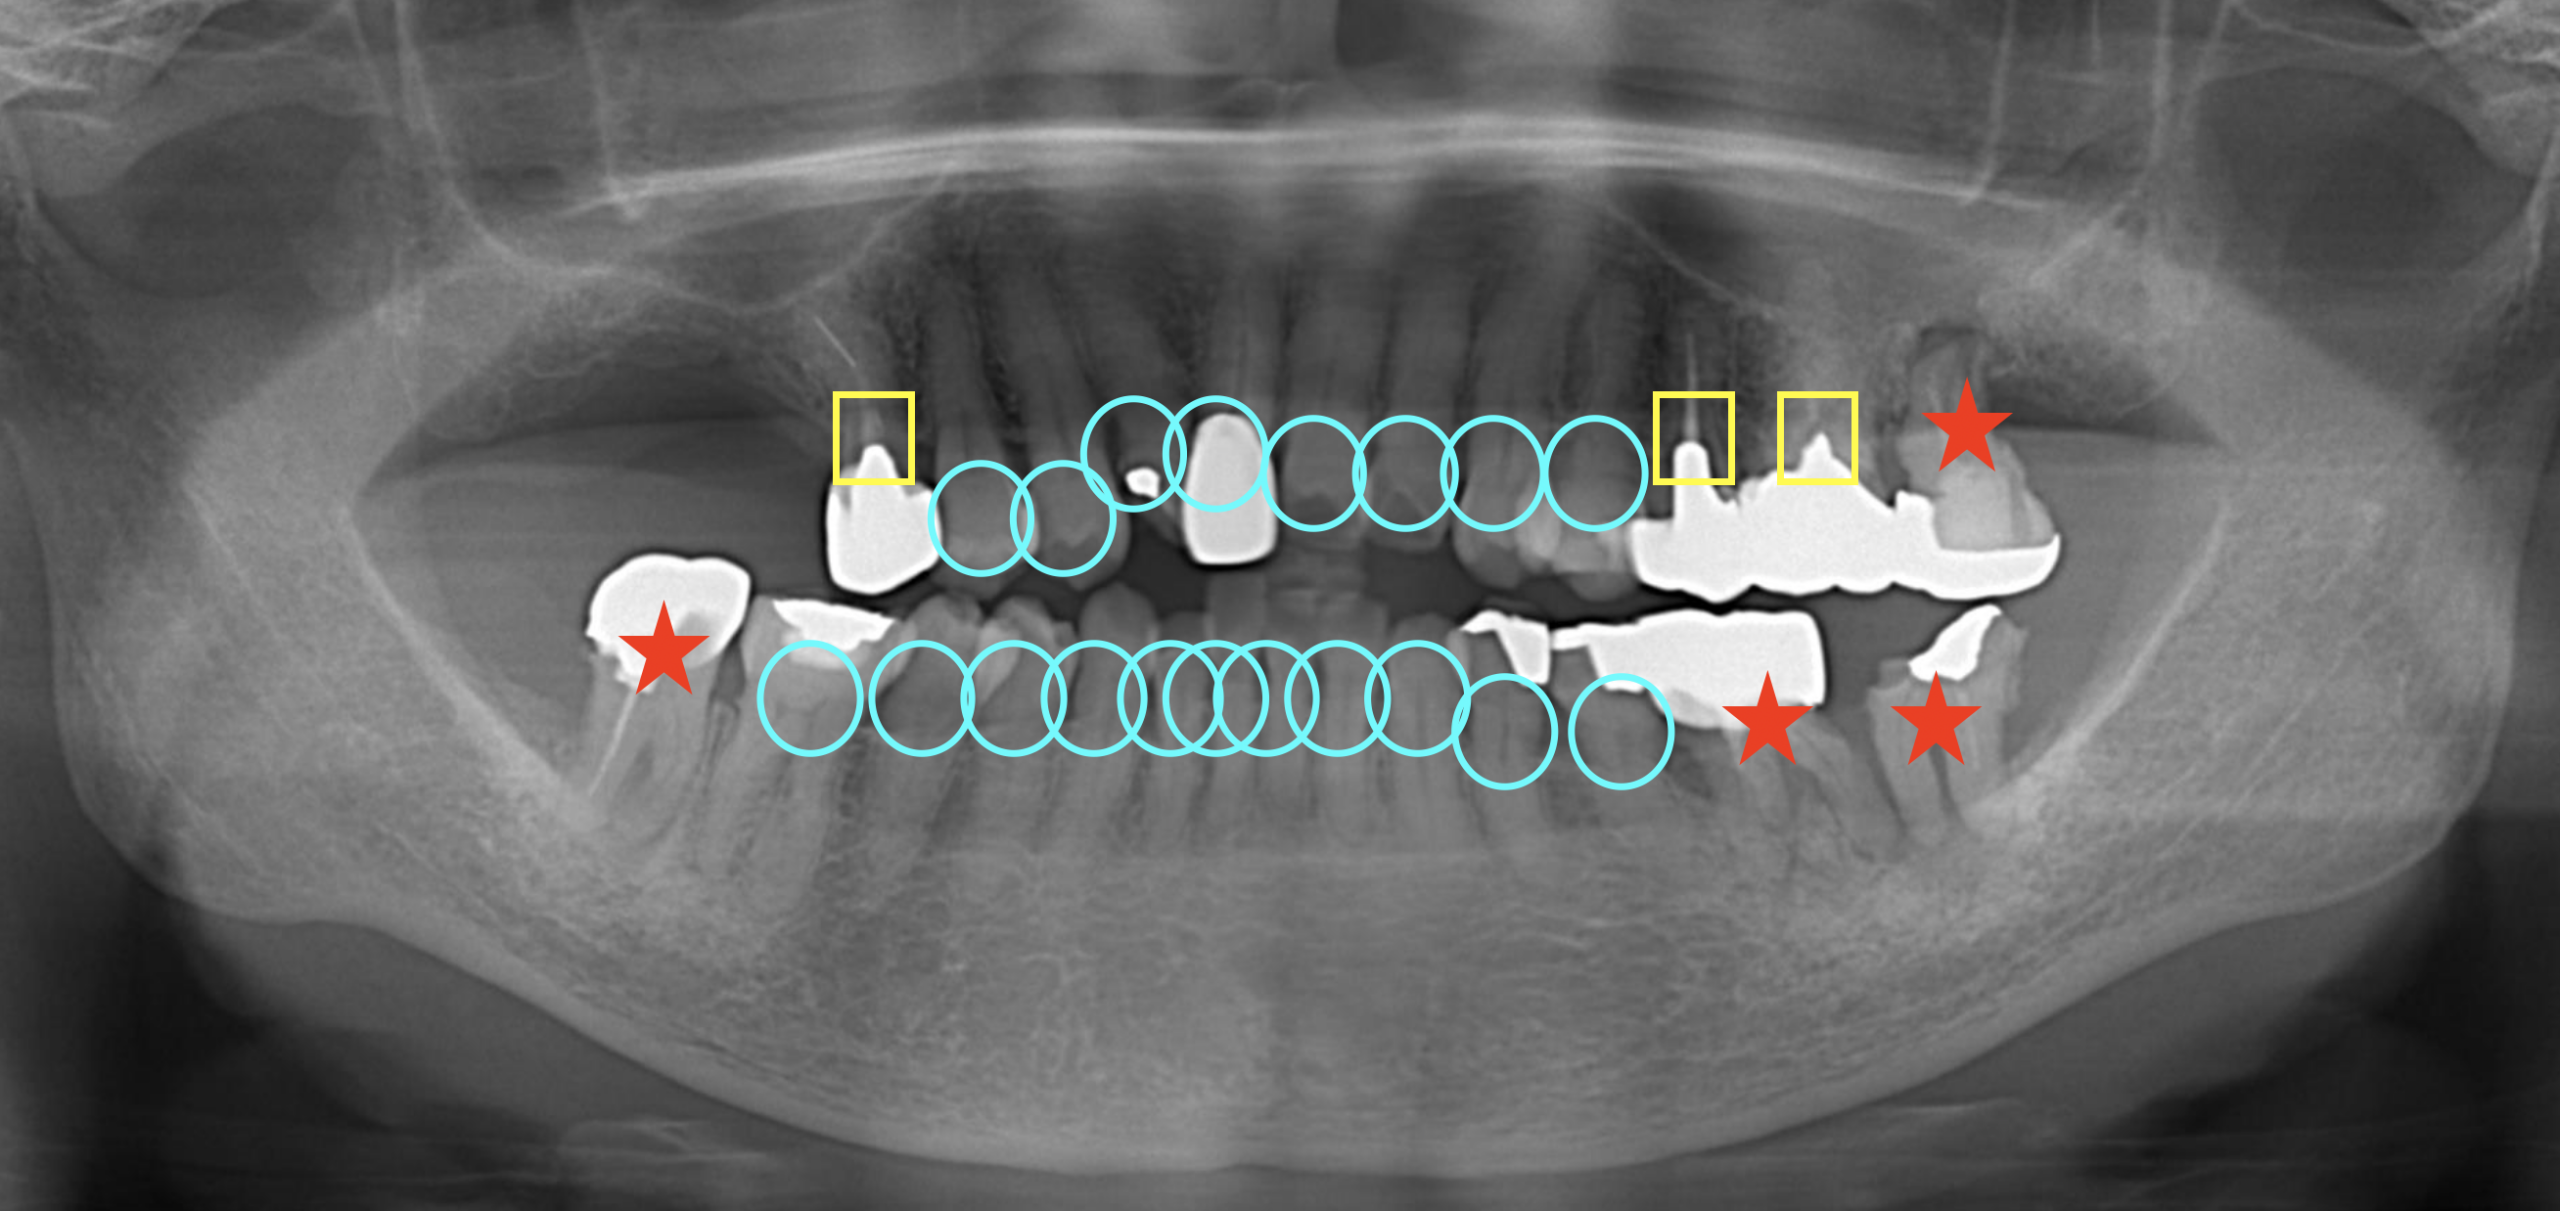

①まずは1本1本の歯の状態を考えます。

全ての歯の条件は当然等しいことはまず無く、1本1本の歯の状態に差があります。

今回で言うと

:青の丸をつけた歯はおそらく最後まで残ると予想される歯

:黄の四角をつけた歯はいつか何かしらのトラブルが起こるだろうと予想される歯

:赤の星をつけた歯は現時点でいつ症状が出てもおかしくない、もしくは寿命が短いと予想される歯

となります。

②次に噛み合わせを考えます。

レントゲンから前歯が噛んでいない、開咬状態だということがわかります。アンテリアオープンバイトと言われる状態です。

噛み合わせの話は非常に難解で、流派によっても意見が変わるため詳細は割愛しますが、開咬は奥歯に非常に不利で、天然の自分の歯ならまだしも、人工物が入ると奥歯が悪くなりやすい状態です。

今回の場合第2大臼歯までを補うのではなく、第1大臼歯までを補う範囲とします。